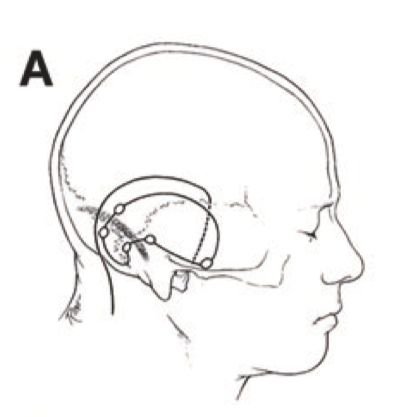

图A: 采用幕上-幕下联合入路,颞枕联合皮瓣,在颞部行低位颞部骨瓣开颅。

图B:病人采取侧卧位,应根据人体的四个生理弯曲及身体轴线,避免过度拉伸及屈曲,同时尽可能缓解压力集中的压迫点压力。

图C:切除在颞枕区域至枕下区域延伸的L形骨瓣后,沿着乳突周围外层开始逐步完成乳突切除术。骨瓣大小取决于听力状况和基础暴露的需要。

图D:硬脑膜切口设计

图E: 打开硬膜,避免损伤横-乙状窦及Labbé静脉,该区域后颞叶的静脉引流存在变化(有时是多种多样的),结扎上岩窦后,并确保颞叶的引流通畅,沿着岩骨尖分离天幕,定位并注意保护滑车神经等。

图F:在分离、暴露、切除肿瘤过程中,注意保留所有颅神经及重要血管。

图G:肿瘤成功全切,神经组织保存完好。